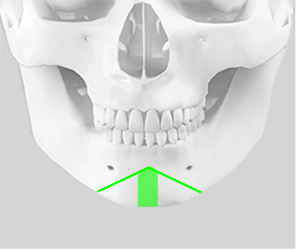

기존의 턱끝 수술 방법인 T절골술은 턱끝의 길이를 조절할 수 없으며,

절골선이 신경과 치아뿌리에 가까워 신경이나 치아 손상의

위험이 높습니다. 2009년 김태규 대표원장은 기존의

T절골술의 단점과 한계점을 개선한 ㅅ절골술을 직접 개발 하여

안전하고 효과적인 턱끝 수술이 가능합니다.

1. 귀 앞부분의 옆광대를

절골

2. 턱끝 중간뼈를 제거하여

턱끝의 길이 조절

3. 티타늄 플레이트와 나사를

사용하여 튼튼하게 고정

4. 입꼬리 사각턱 절제술 및

외측피질 쉐이빙 시행